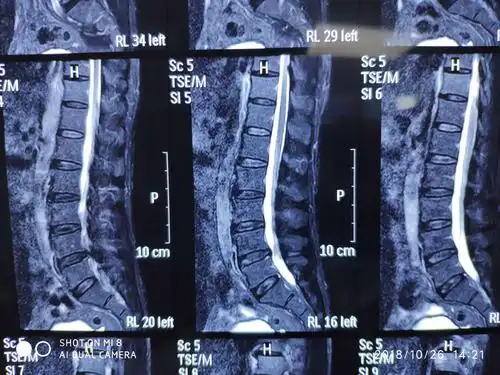

大通道脊柱内镜下经椎板间隙单侧入路双侧减压技术治疗腰椎管狭窄症

腰椎管狭窄病人

术前ct显示横断面椎管严重狭窄